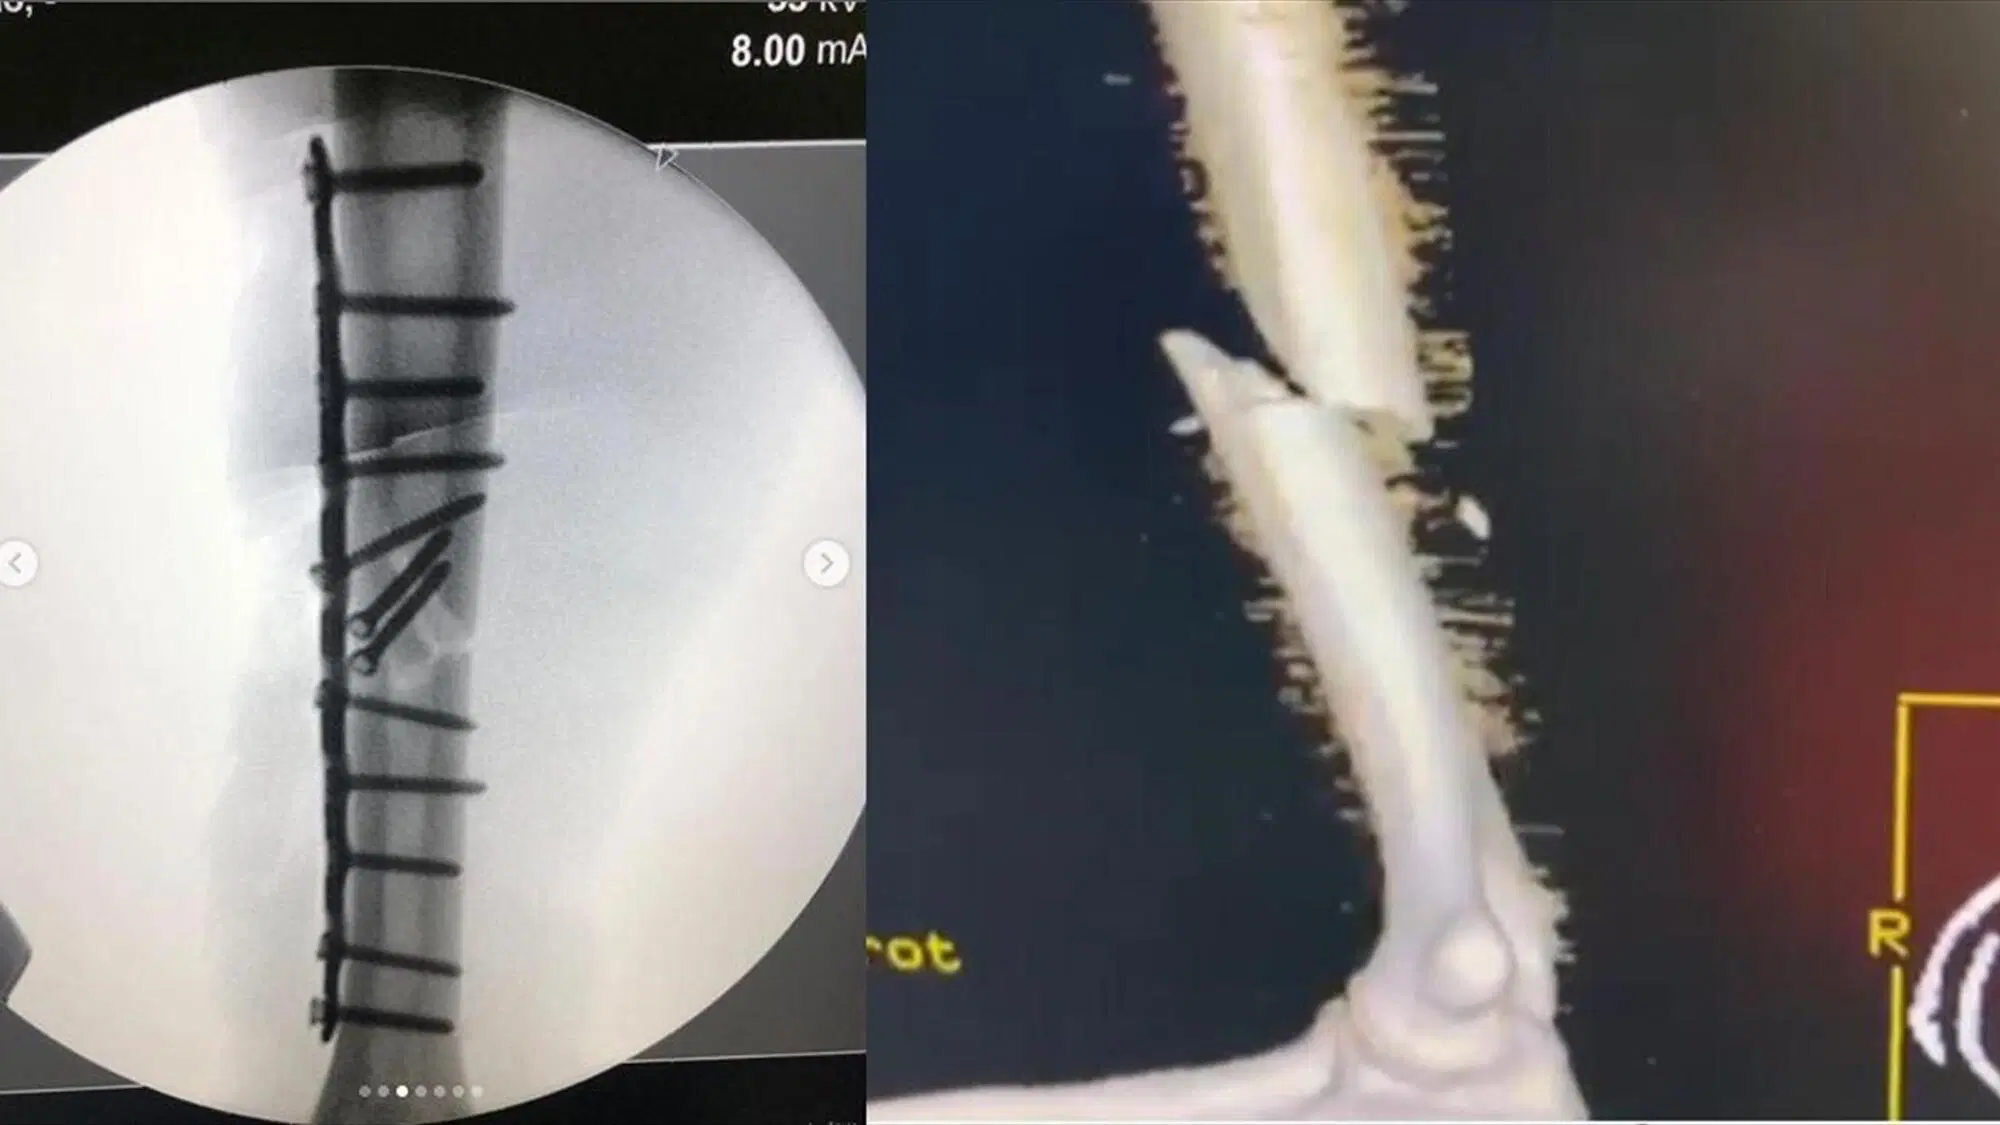

Nel frattempo però lo stesso Marc continua a pubblicare, sui suoi canali social, i progressi della riabilitazione e del duro lavoro per tornare in pista il prima possibile. Quello pubblicato qui sotto è infatti solo l'ultimo tweet dell'otto volte campione del mondo che sembra più intenzionato che mai a dare, come sempre, il meglio di sé.